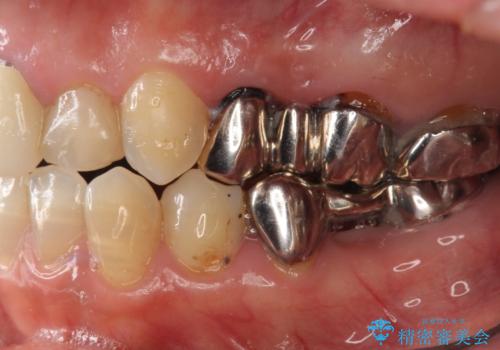

- 銀歯を白くしたいとのことで来院。

左上が特に気になるそうであったためまず左上の奥歯から治療をしていここととなりました。